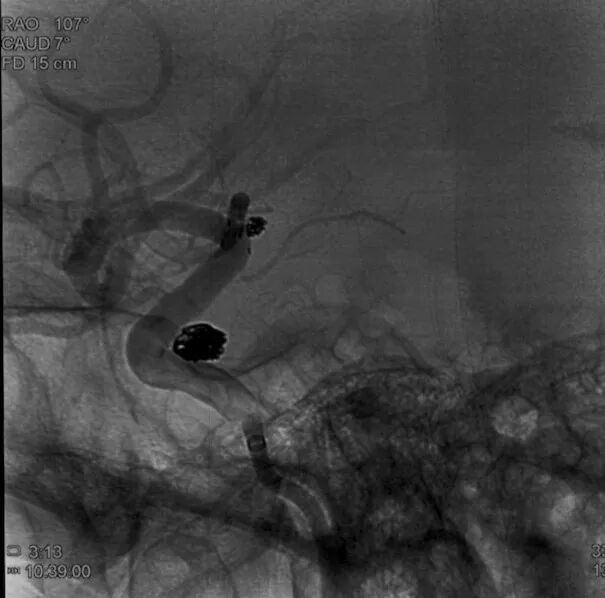

工作位侧位造影(图片)

工作位侧位造影(视频)

6F Envoy DA在泥鳅导丝辅助下超选至右侧颈内动脉海绵窦段后膝。